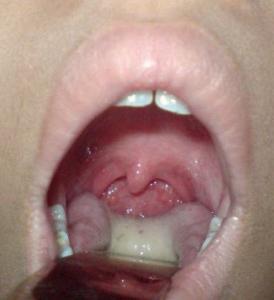

Медицинский специалист, занимающийся лечением общих заболеваний, быстро определяет наличие фарингита при осмотре глотки: слизистая оболочка страдает от отека, имеет ярко-красный цвет и покрыта сероватым налетом, миндалины увеличены, иногда можно увидеть красные точки в форме маленьких бугорков. Фарингит, вызванный стрептококками, почти всегда сопровождается насморком, причем выделения из носа прозрачные и настолько обильные, что могут вызвать размягчение кожи под носом. Пациенту рекомендуется использовать местные средства для обеззараживания горла в виде спрея или леденцов, необходимости в приеме антибиотиков внутрь нет.

- Отек и покраснение слизистой оболочки глотки;

- Увеличение размеров миндалин;

- Появление на слизистой оболочке горла рыхлого сероватого или желтоватого налета, а также возможность образования гнойных пробок;